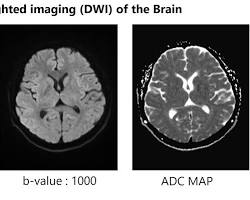

صورة توضيحية:

صورة DWI brain scan

DWI brain scan

في هذه الصورة، يمكن رؤية المناطق المصابة بالسكتة الدماغية بشكل واضح، حيث تظهر كمناطق ذات إشارة منخفضة.